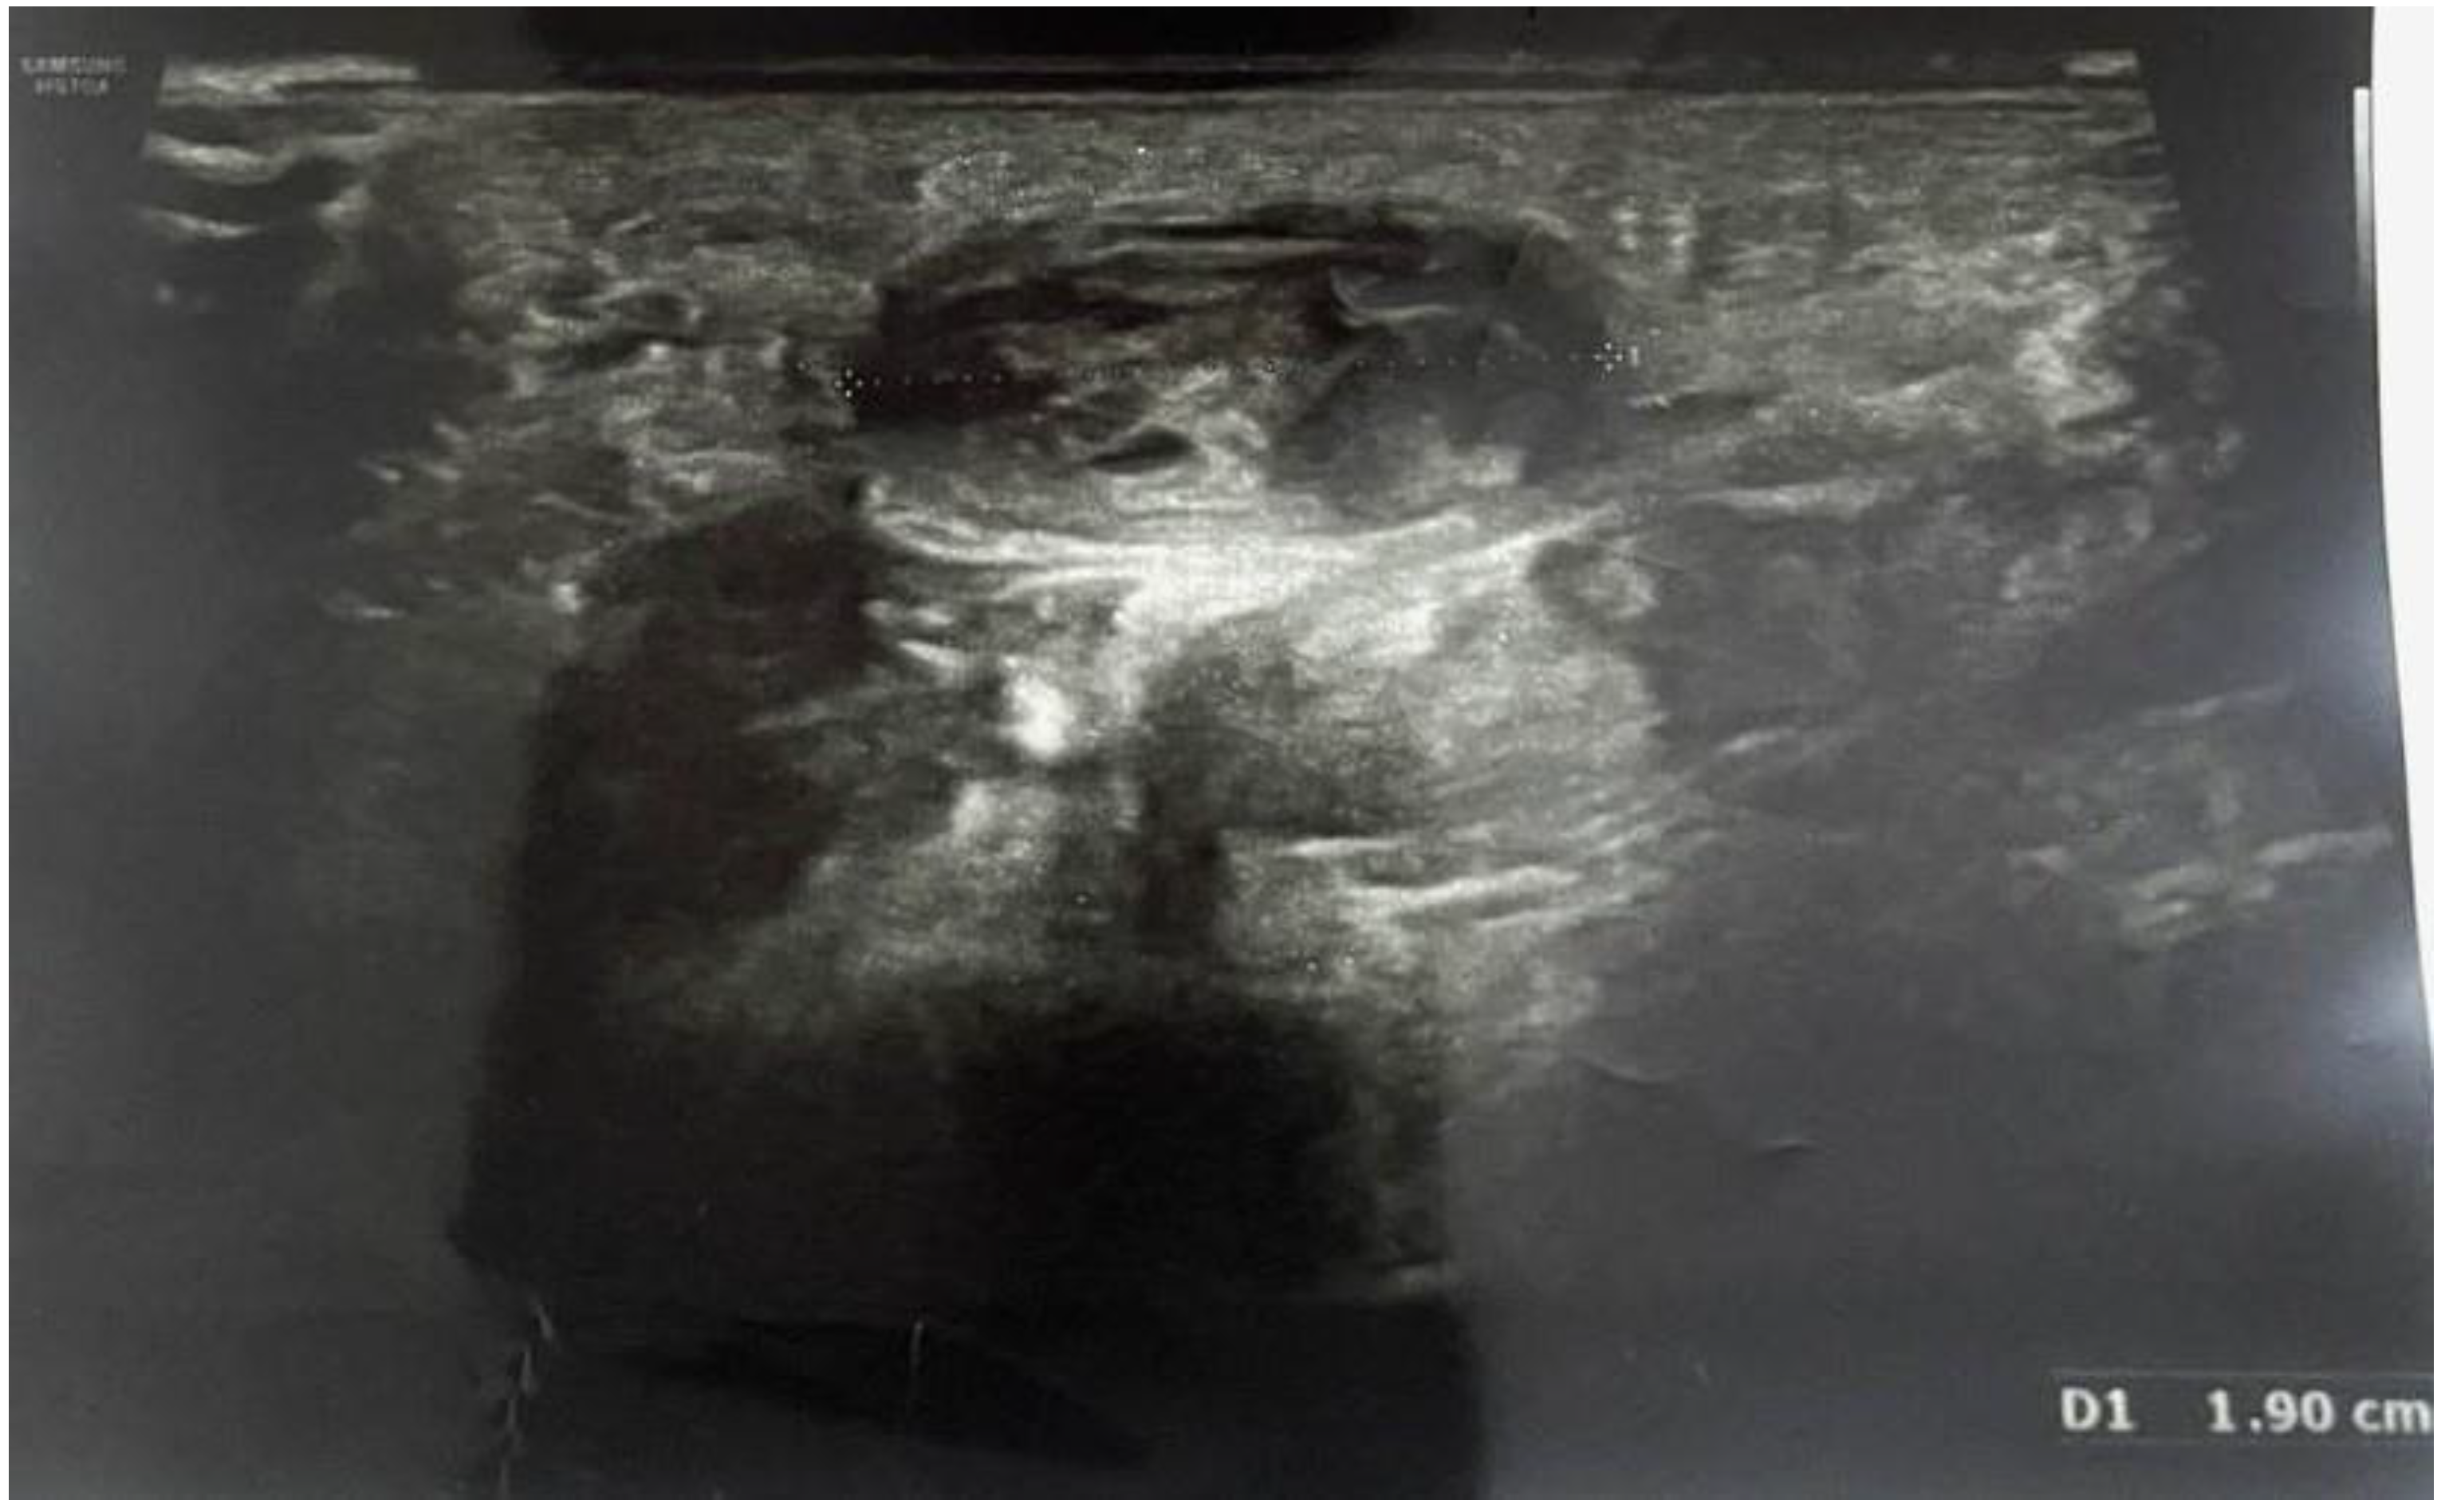

Pain, discomfort and paresthesia were present for over 1.5 years. Ultrasound imaging allowed the diagnosis of an ulnar artery aneurysm of approximately 19 mm (Figure 1)

Figure 1. Preoperative ultrasonography, D1 shows the length of ulnar artery aneurysm (19mm).